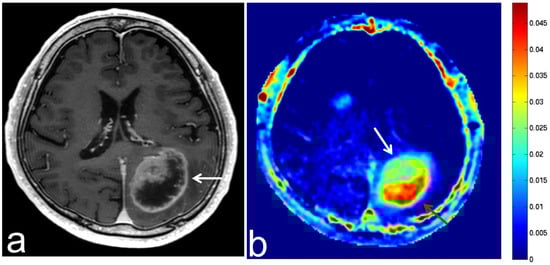

5.5. Brain Metastasis